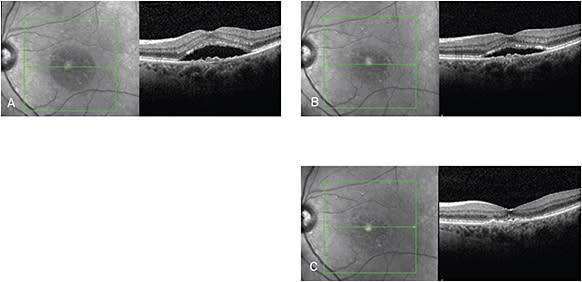

Figure 2. Right eye before treatment (A) and 1-month post-aflibercept treatment (B).

Figure 1. Left eye before treatment (A), 5 days after treatment with aflibercept (B), and 1-month post-aflibercept treatment (C).